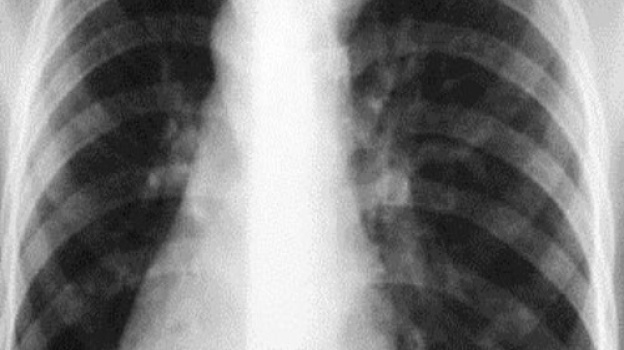

Рентгеновские снимки при пневмоцистной пневмонии